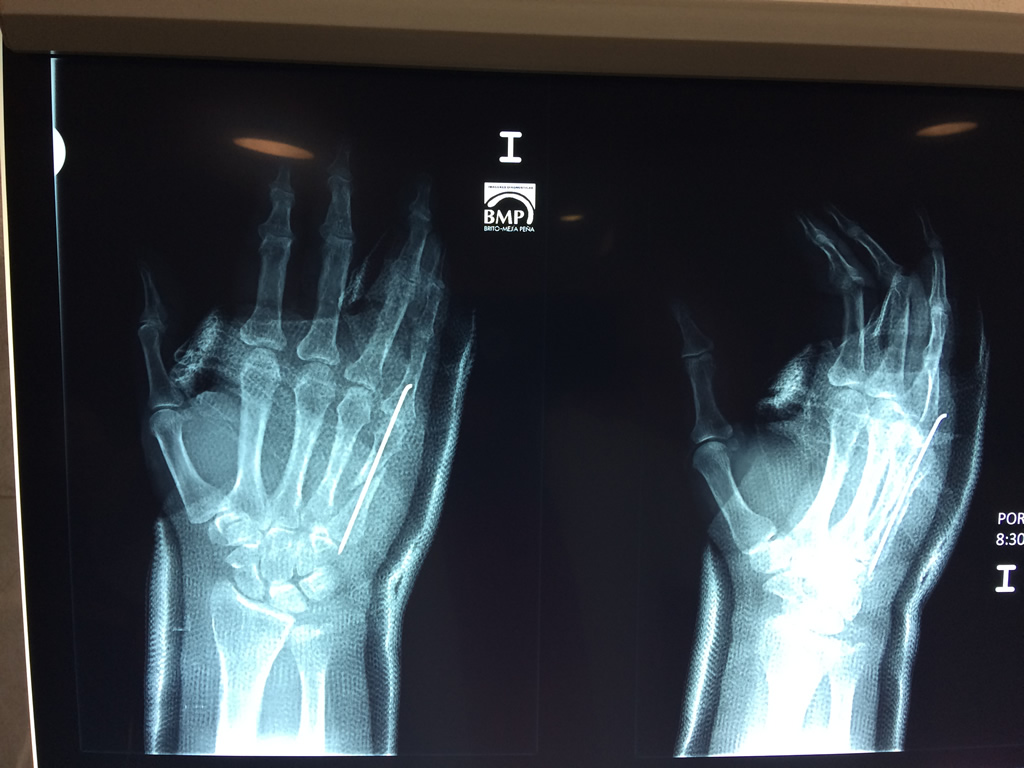

Cirugías de Húmero - Cirugías de Muñecas y Manos

Los procedimientos más comunes en cirugía de la mano son aquellos destinados a reparar traumatismos, incluyendo lesiones de tendones, nervios, vasos sanguíneos, y articulaciones; huesos fracturados; y quemaduras, cortes, y otros daños de la piel.